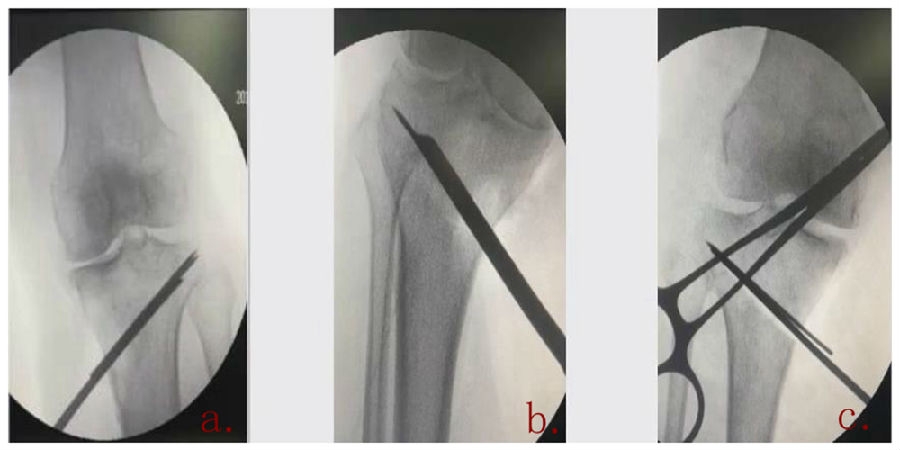

a.合理;b.过低(Ⅱ型);c.过高(Ⅰ型)

(2)合页宽度

合页具有一定的变形能力,同时还有一定的强度,一般要保留1cm左右的宽度。如果合页保留过宽,那么此时合页强度过强,而变形能力不够,在过度撑开时会出现骨折,易造成Ⅲ型骨折。如果合页保留过窄,就会容易截过了,容易出现Ⅰ型骨折。所以强调合页宽度要求要在1cm左右,这样才具有一定的稳定性,同时还有一定的变形能力。

a.合理;b.过宽(Ⅲ型);c.过窄(Ⅰ型)